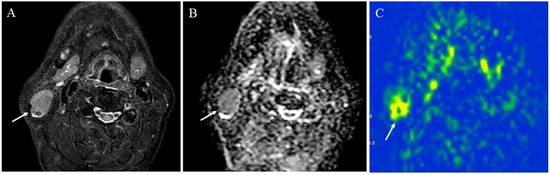

5.1.3. Salivary Gland Tumor Differentiation: Malignant Salivary Tumors, Pleomorphic Adenomas, and Warthin’s Tumors

- Tanaka, F.; Umino, M.; Maeda, M.; Nakayama, R.; Inoue, K.; Kogue, R.; Obara, M.; Sakuma, H. Tumor blood flow and apparent diffusion coefficient histogram analysis for differentiating malignant salivary tumors from pleomorphic adenomas and Warthin’s tumors. Sci. Rep. 2022, 12, 5947. [Google Scholar] [CrossRef]

- Yamamoto, T.; Kimura, H.; Hayashi, K.; Imamura, Y.; Mori, M. Pseudo-continuous arterial spin labeling MR images in Warthin tumors and pleomorphic adenomas of the parotid gland: Qualitative and quantitative analyses and their correlation with histopathologic and DWI and dynamic contrast enhanced MRI findings. Neuroradiology 2018, 60, 803–812. [Google Scholar] [CrossRef]